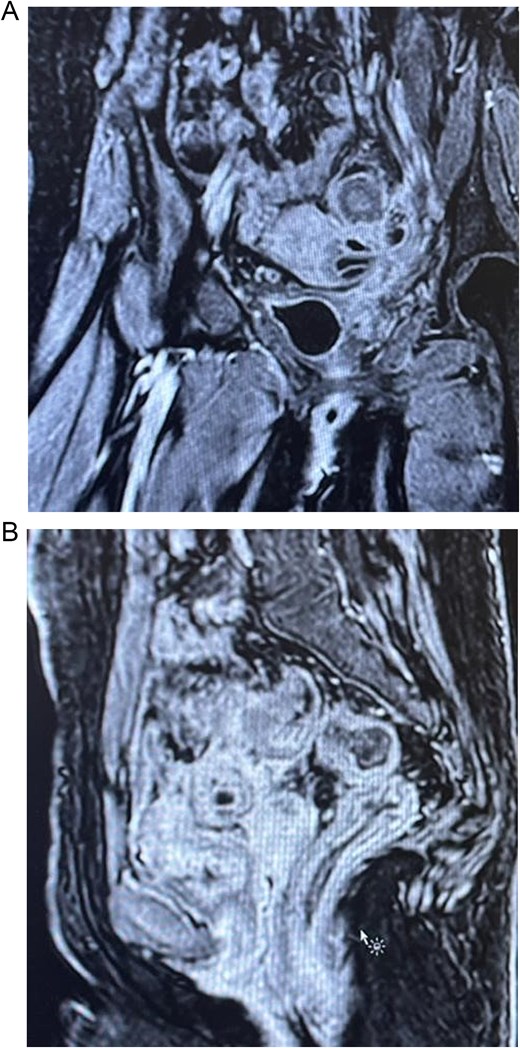

Colonoscopy showed severe luminal narrowing between the junction of the sigmoid and descending colon. Diagnostic cystoscopy confirmed the presence of a fistula opening and demonstrated a villous-like reaction in the urinary bladder mucosa, consistent with a fistulous connection. The fistula opening was located low, raising the possibility of vesicovaginal fistula. Magnetic resonance imaging (MRI) of the abdomen conformed sigmoid diverticulitis and fistula tract to urinary bladder and also possibly a fistula tract extending to the mid-rectum (Fig. 2).

(A) Axial section of the abdominopelvic CT scan showing the colovesical fistula. (B) Axial section of the abdominopelvic CT scan showing the diverticular disease of the colon.